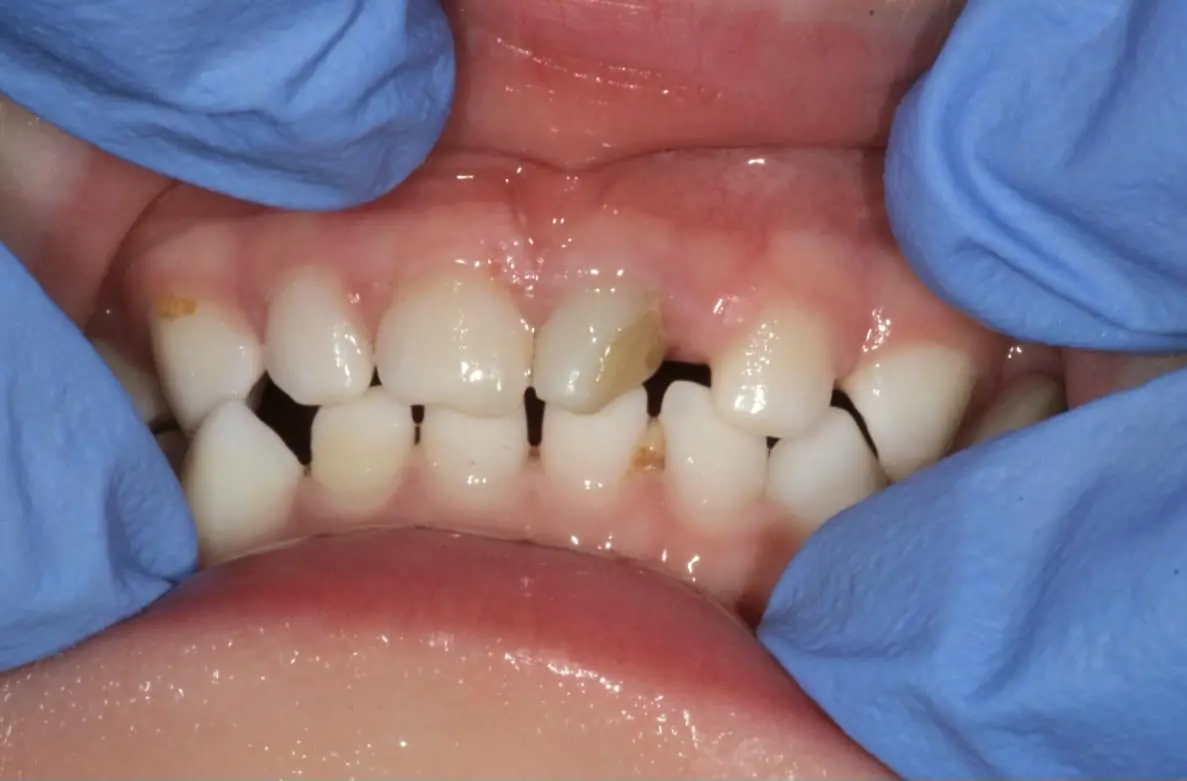

Травма - те, що може статися з будь ким і в будь який момент. А особливо це стосується дітей, які починають активно освоювати навколишнє середовище. Тому знати і вміти зреагувати на травму тимчасового зуба є стратегічно важливим для дитячого стоматолога.

Нерідко, на жаль, трапляються ситуації, коли діти травмують тимчасові зуби. В такому випадку часу на роздуми, як правило, не так багато. Рішення потрібно приймати швидко, часу на підготовку, як правило немає. Саме тому дитячому стоматологу потрібно розуміти, що потрібно робити, а що робити не потрібно. Травми коронкової частини і кореня, навколишніх тканин - що, як і коли робити? В якому випадку терміново втручатись, як коли спостерігати.